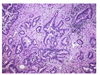

What kind of lung cancer is this?

Adenocarcinoma

Most common histology of NSCLC

A for Adeno - A lot, Anyone, Anywhere (central or peripheral)